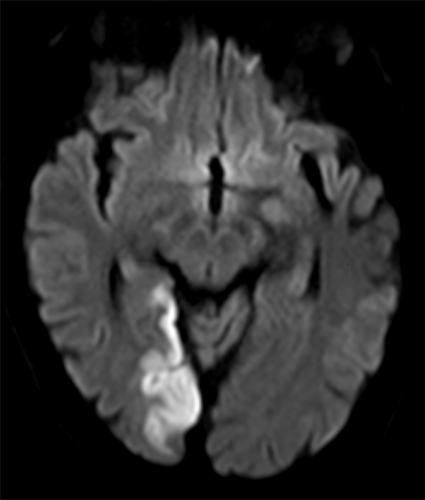

À l’examen clinique : la patiente est désorientée. Elle a une amputation dans les hémichamps visuels gauches des deux yeux. Le testing moteur vous semble légèrement plus faible aux deux membres inférieurs, vous ne parvenez pas à évaluer la sensibilité. Ses réflexes ostéo-tendineux sont vifs aux membres inférieurs, vous retrouvez une extension lente des deux hallux lorsque vous effleurez la plante des pieds avec votre marteau. Lorsque vous regardez les chaussures de la patiente, il vous semble que l’avant de ses chaussures est très abîmé par rapport à l’arrière.